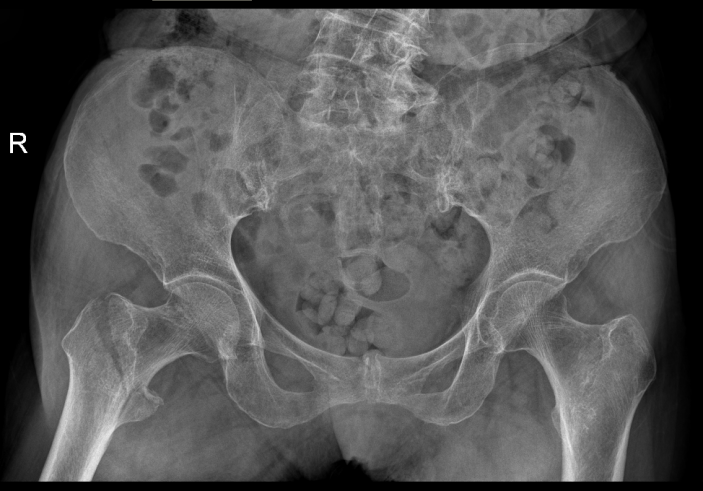

△骨科于15日、16日收治的另外兩位高齡患者

△術前